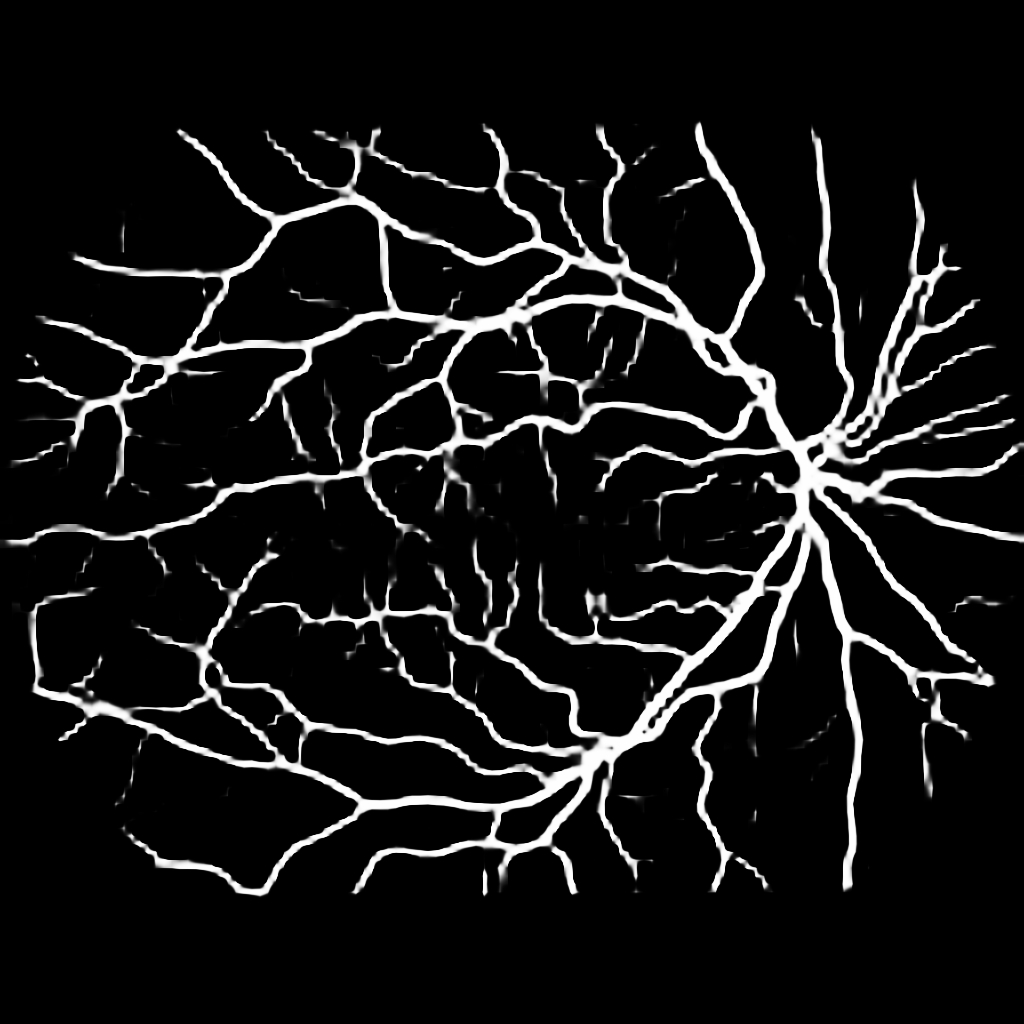

For completeness, and to test the robustness of our method, the models were also tested with several images sourced from Google™. We purposefully sourced extremely poor quality images (i.e. images with low contrast, speckle artefacts, etc), as well as images of pathological cases (i.e. Exdudates, Hemorrhages, etc). As there are no ground truth labels, only a qualitative assessment can be made of the results shown in Figure 2. In all cases, the models have accurately segmented the vessel structure whilst ignoring imaging artifacts and pathological lesions. This is very evident in the case of (5) and (6) where no vessels were segmented in areas of severe hemorrhaging.

{L to R: (1) Healthy, (2) Unhealthy, (3) Speckle Artefacts, (4) NPDR, (5) PDR, (6) Hemorrhages}